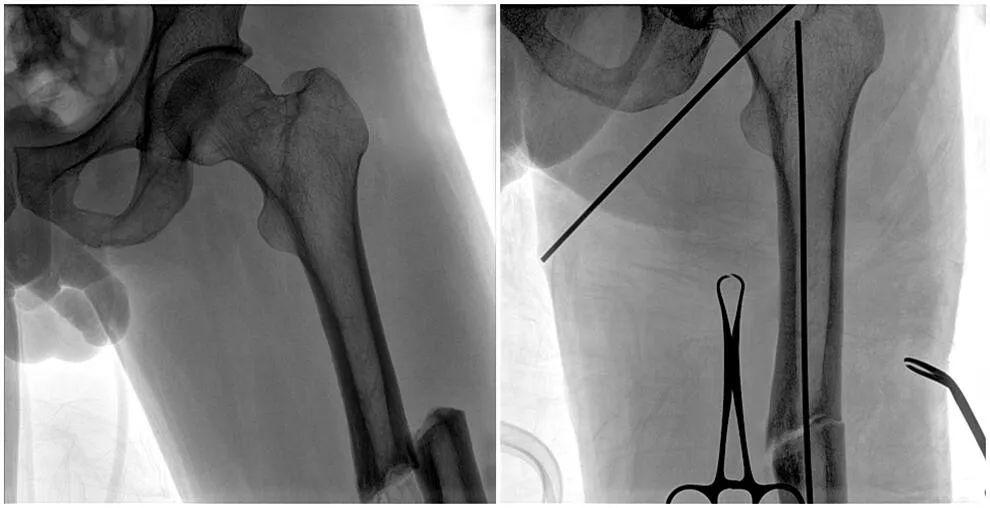

C形臂輔助手術(shù)過程

術(shù)中使用普愛醫(yī)療大平板一體式C形臂進(jìn)行透視,判斷骨折情況及克氏針、髓內(nèi)釘?shù)冉饘僦踩胛锏奈恢茫M(jìn)行調(diào)整。C形臂準(zhǔn)確的術(shù)中定位,大大縮短了手術(shù)的時(shí)間,減輕了患者的痛苦,輔助手術(shù)順利完成。

在進(jìn)行髓內(nèi)釘內(nèi)固定術(shù)時(shí),醫(yī)生需要同時(shí)觀察到入釘點(diǎn)和骨折部位的情況,普愛醫(yī)療大平板一體式C形臂采用30CM×30CM的平板探測器,能夠呈現(xiàn)更廣闊的成像面積,滿足大部分長骨髓內(nèi)釘內(nèi)固定術(shù)的攝片需求。